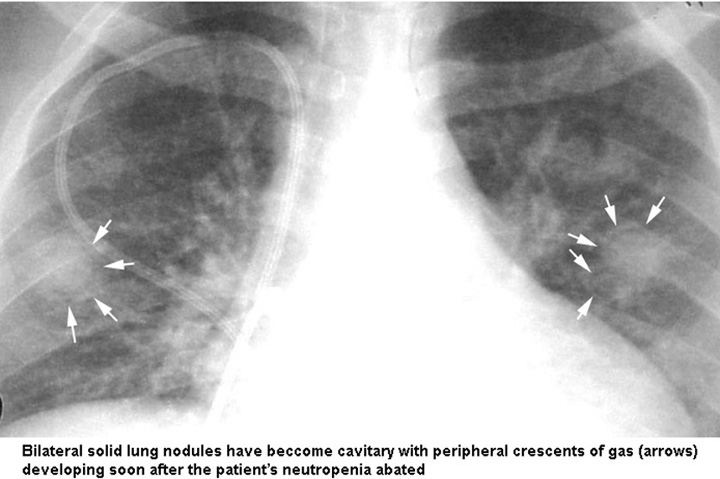

Визуализация и диагностика неинвазивного аспергиллеза с помощью КТ

Раздел: Необычные решения